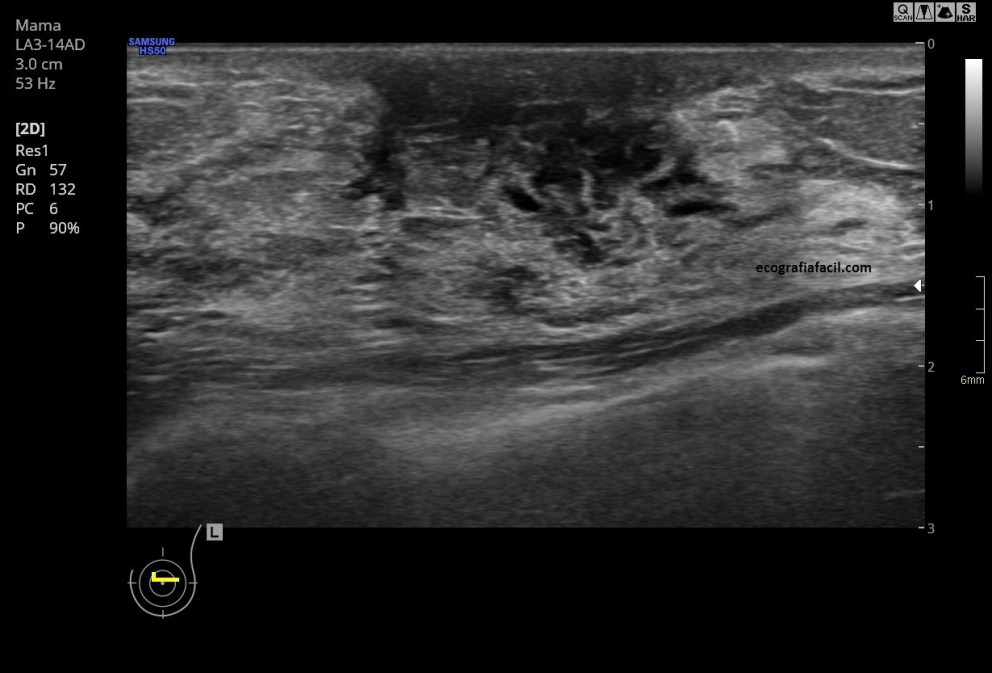

En la figura 1 y 2 vemos una imagen de la región retroareolar, en la imagen 2 ves claramente los conductos dilatados alargados y anecoicos tras del pezón.

In figure 1 and 2 we see an image of the retroareolar region, in image 2 you see clearly the dilated ducts.